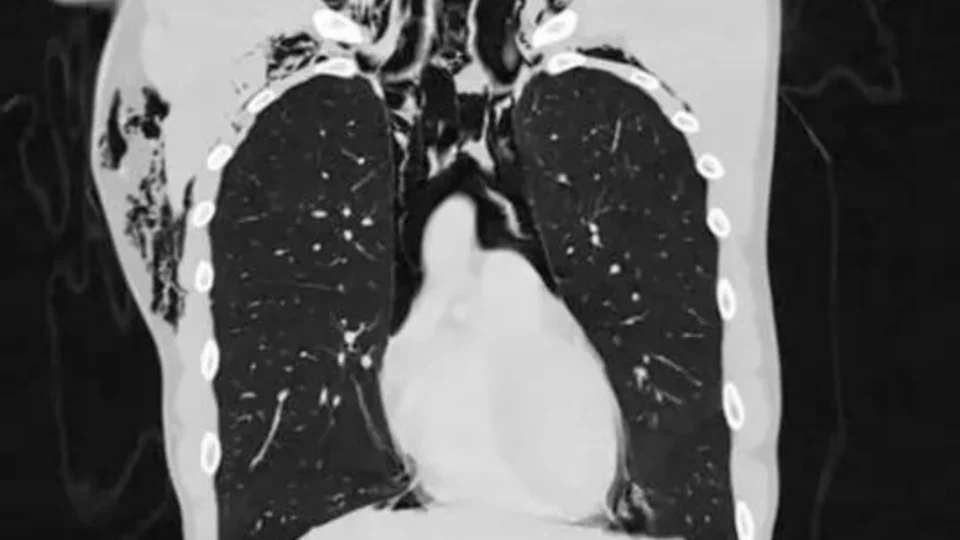

Ao realizar exames, os médicos identificaram um enfisema subcutâneo (presença de ar nos tecidos sob a pele) e a tomografia computadorizada da região revelou o diagnóstico de pneumomediastino espontâneo.

De acordo com a revista científica, o diagnóstico de pneumomediastino espontâneo, também conhecida como Síndrome de Hamman, é raro e normalmente a doença é desencadeada com esforço intenso, tosse ou vômito.